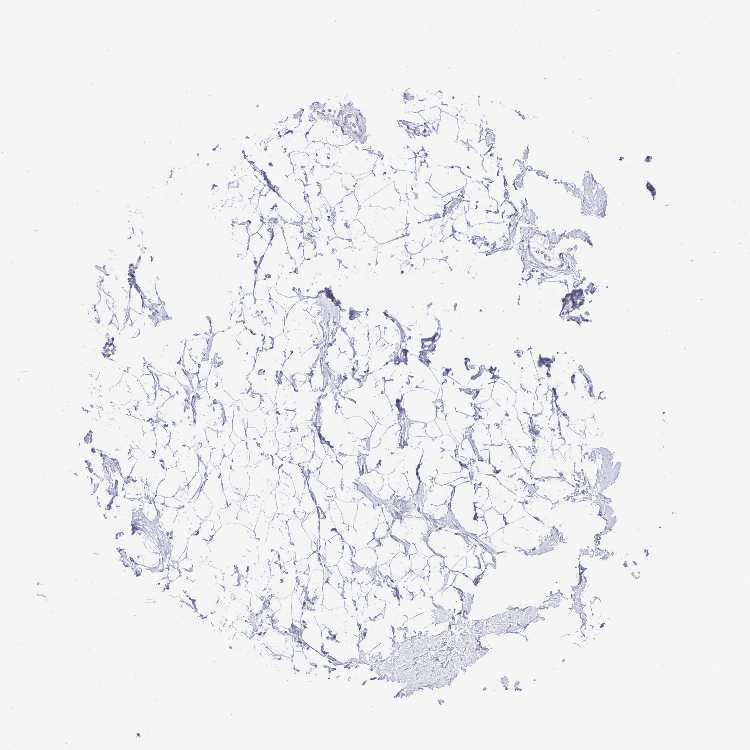

BREAST - Antibody stainingi

Antibody staining in the annotated cell types in the current human tissue is reported as not detected, low, medium, or high, based on conventional immunohistochemistry profiling in selected tissues. This score is based on the combination of the staining intensity and fraction of stained cells.

Each image is clickable and will lead to virtual microscopy that enables deeper exploration of all samples and also displays staining intensity scores, fraction scores and subcellular localization as well as patient and tissue information for each sample.

Antibody HPA045715Antibody HPA056466Antibody CAB003697

Adipocytes Not detectedNot detectedNot detected

Glandular cells Not detectedNot detectedNot detected

Myoepithelial cells Not detectedNot detectedNot detected